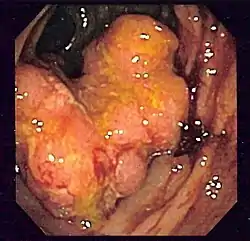

- Colonoscopie : c'est l'examen de référence. Une sonde (long flexible enrobé de plastique) est insérée par l'anus puis glissée peu à peu dans l'intestin. Il permet d'observer la muqueuse et de faire des prélèvements ; si l'on constate un polype, celui-ci est enlevé entièrement et sera analysé au laboratoire par histologie, et son exérèse diminue beaucoup le risque de cancer. La sigmoïdoscopie, un examen plus rapide et moins complet, utilise une courte sonde semi-rigide, qui permet l'exploration du rectum et du colon sigmoïde.

On trouve le plus souvent dans l'intestin des adénomes (= polypes adénomateux). Considéré comme bénin, le polype risque d'évoluer vers un cancer si on le laisse en place, s'il est gros (plus d'un centimètre de diamètre), et/ou s'il est villeux (=avec des villosités). Les petits polypes et les polypes tubulaires présentent moins de risques. On trouve aussi des polypes hyperplasiques, considérés comme pratiquement sans risque. Enfin on trouve dans les colons des adénocarcinomes, qui sont les véritables cancers, dont les cellules dysplasiques franchissent la lamina propria. Ce premier stade de l'invasion peut évoluer pour s'étendre à d'autres organes et conduire à l'apparition de métastases, hépatiques le plus souvent, qui provoquent la mort plus fréquemment que la tumeur initiale.